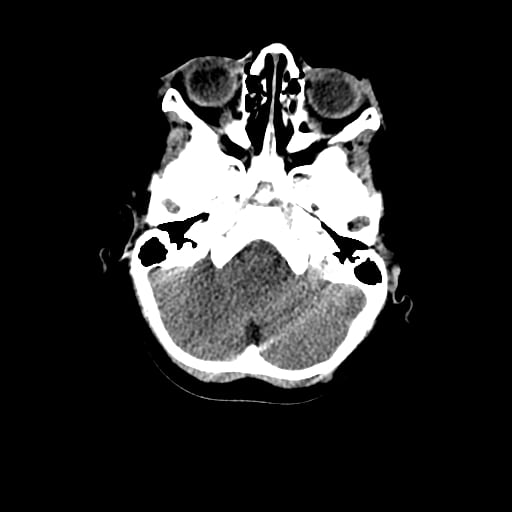

Age: 1

Sex: Male

Indication: Fall